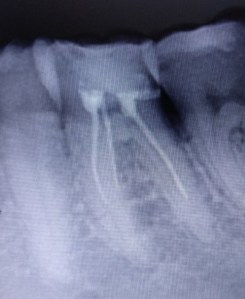

Előfordul, hogy egy korábban gyökértömött fogat újra kell gyökérkezelnünk, mert befertőződött.

Egy gyökértömés befertőződése lehet akár észrevétlen, panaszmentes is.

Előbb-utóbb azonban, ha a gyökértömés nem jól “zár”, a csatornába jutott, vagy onnan nem eltávolított kórokozók gyulladást; fájdalmat, duzzanatot okoznak.

A kezelés célja, hogy a gyökércsatornákba jutott, vagy ottrekedt baktériumokat eltávolítsuk és a csatornarendszer hermetikus lezárásával megakadályozzuk annak újbóli befertőződését.

Ennek kivitelezéséhez eltávolítjuk a régi gyökértömést, majd esetlegesen “meg nem talált” csatornákat keresünk. Mechanikai megmunkálással tovább tágítjuk a gyökércsatornát, illetve fertőtlenítő átöblítéssel közel csíramentessé tesszük a csatornarendszert.

Ezután jellemzően 1-6 hét szünet jön, majd panaszmentesség esetén hermetikusan lezárjuk a csatornákat.